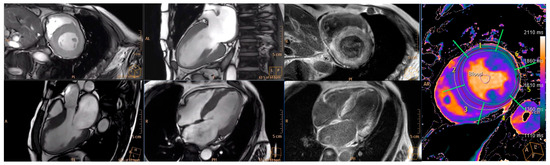

3.5. Changes in Cardiac Magnetic Resonance Parameters

Appendix A.3. Cardiac Magnetic Resonance Protocol and Image Analysis

Appendix A.4. CMR Analysis

| Cardiac Magnetic Resonance | |||

| LVEF (%, ± SD) (n = 9) | 56 ± 7.2 | 59 ± 8.3 | 0.376 |

| LVMi (g/m2, ± SD) (n = 9) | 53.2 ± 32.3 | 71.3 ± 36.0 | 0.139 |

| Native T1 (ms, ± SD) (n = 9) | 1424.9 ± 51.9 | 1446.9 ± 54.8 | 0.004 |

| Post-contrast T1 (ms, ± SD) (n = 9) | 524.8 ± 68.1 | 499.7 ± 52.9 | 0.130 |

| ECV (%, ± SD) (n = 9) | 40.7 ± 8.3 | 42.7 ± 9.4 | 0.415 |

| T2 (ms, IQR) (n = 9) | 55.3 (52.7–58.7) | 58.8 (54.6–60.2) | 0.401 |